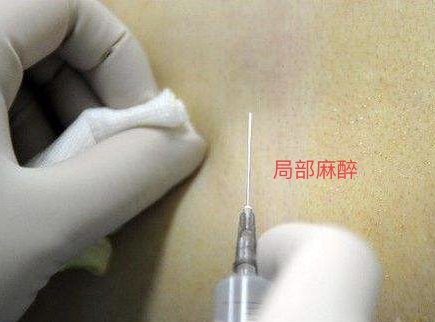

局部麻醉

因为椎间孔镜手术大部分都为局麻清醒手术,所以大家最关心的问题之一就是手术疼吗?因此,局部打麻药过程十分重要,麻药打的好以及加上一些镇静药物患者基本痛感十分轻微,完全可以耐受。